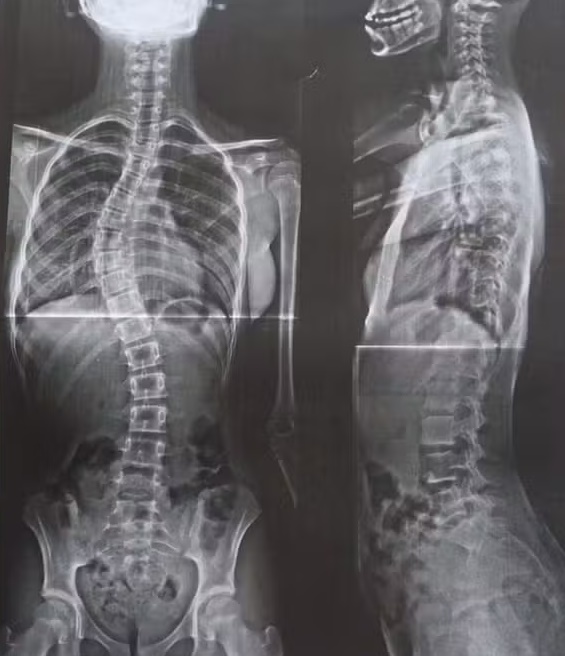

RONDÔNIA - A batalha de uma mãe para garantir o direito à saúde da filha de 12 anos tem chamado atenção em Rondônia. Diagnosticada com escoliose progressiva, doença que fez a coluna atingir uma curvatura de 52 graus — considerada grave —, a adolescente Sophia Laborda enfrenta dores constantes e limitações no dia a dia.

Médicos explicam que a escoliose idiopática, de origem genética e rara, costuma surgir durante a fase de crescimento, podendo evoluir de forma silenciosa. Quando ultrapassa 40 graus de curvatura, a cirurgia é a única alternativa eficaz, devendo ser realizada em centros especializados, com equipe multidisciplinar.